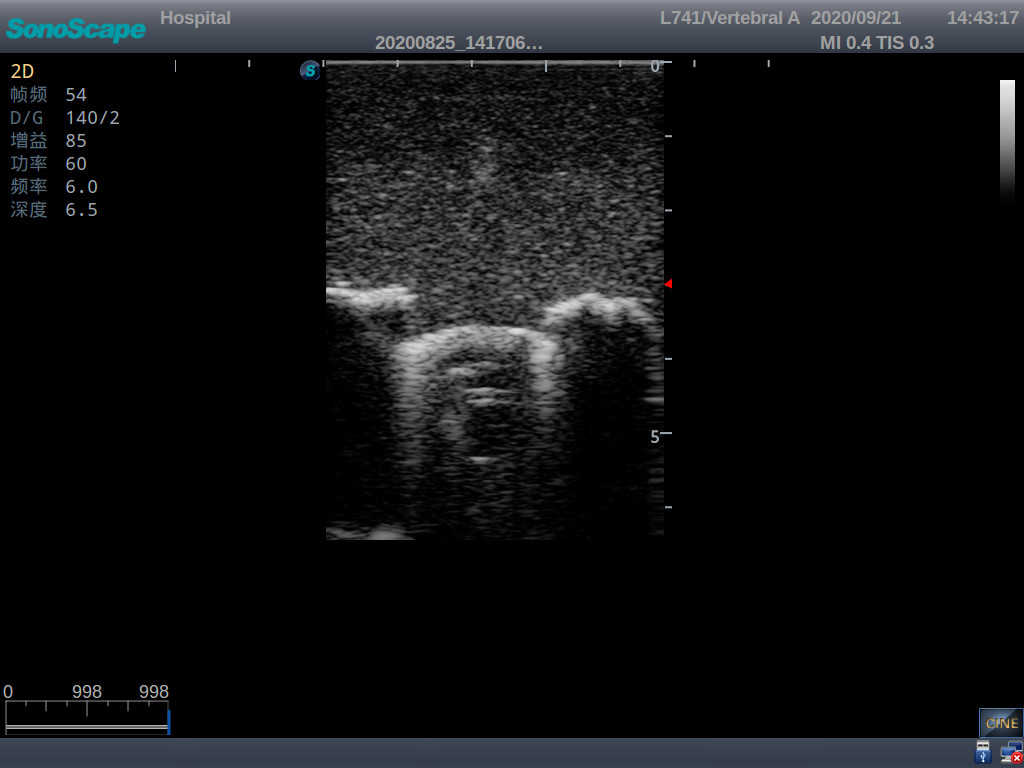

Pediatric Lumbar Puncture Ultrasound Training Model

This model is an ideal choice for ultrasound-guided pediatric lumbar puncture training with true-to-life skin feel and touch, accurate anatomical structures as well as real clinical ultrasound images. Realistic resistance to needle tips and correct landmarks provide excellent hands-on experience.

2)  Real clinical ultrasound images